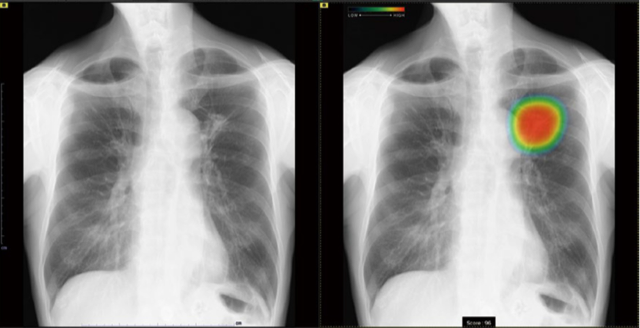

胸部レントゲン(AI機能付き)

胸のレントゲン検査にAI技術を導入しています。

当クリニックでは、胸のレントゲン検査(胸部X線)を受けていただいた際に、医師の目に加えてAI(人工知能)による画像チェックも行っています。

導入しているのは、富士フイルムの「CXR-AID」という医療用AIで、レントゲン画像から「肺の影」「炎症のような変化」「気胸(肺のしぼみ)」など、見つけにくい異常のサインを検出します。

医師が画像を読んで診断を行う際、AIが見つけた部分も参考にすることで、小さな病変の見落としを減らし、より正確な診断につなげることができます。

当院で行うすべての胸のレントゲンにこのAIチェックを行っています。